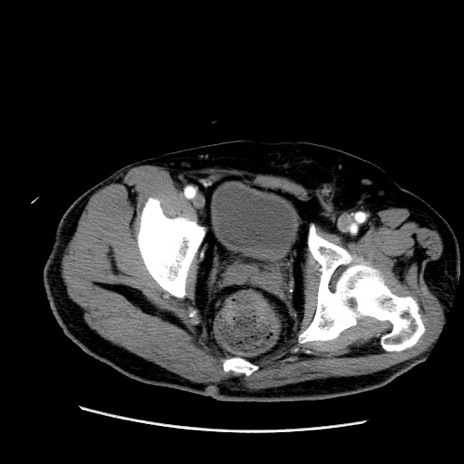

症例22(横断像)

【症例】50歳代男性

【主訴】腹痛

【現病歴】AVMからの被殻出血のため回復期リハ病棟入院中。 本日午後3時頃急に下腹部痛が出現した。

【既往歴】AVM、被殻出血、虫垂炎、高血圧

【身体所見】意識晴明、左半身不全麻痺、会話の理解は良好、36.5°C、腹部:膨隆、全体に板状硬、下腹部正中に圧痛点あり、反跳痛-、筋性防御不明、右下腹部にope scar

【データ】WBC 9400、CRP 0.06